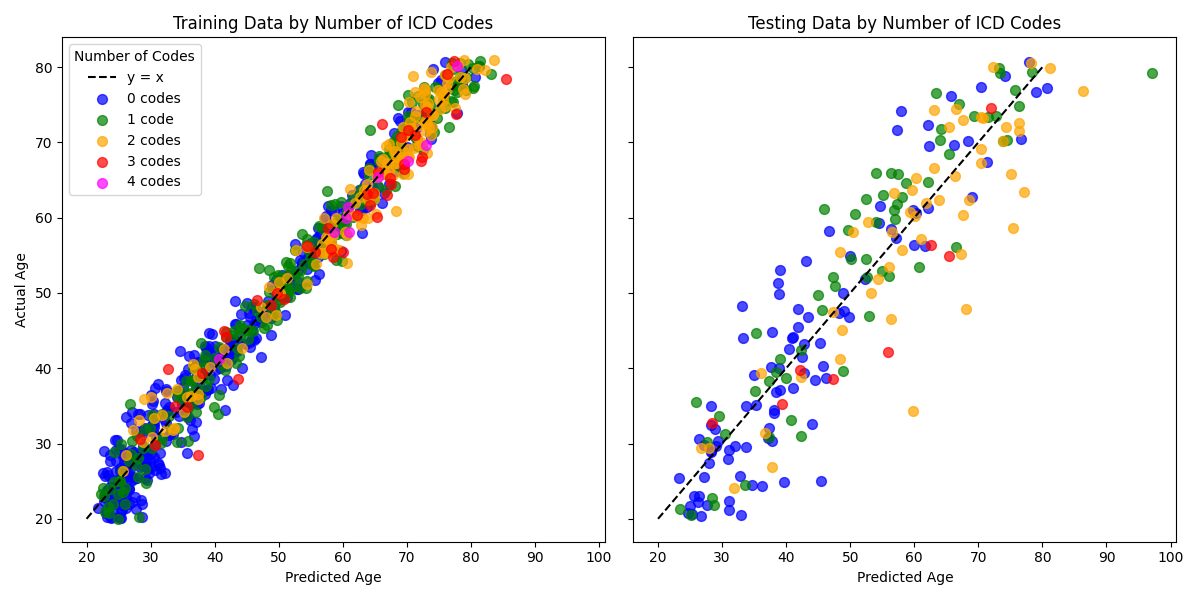

It is important to note that the cross-validation metrics are on-par with those observed in the test set. The training MAE was similar, but the training metric was more exuberant (0.97). This means we do have mild evidence of overfitting to the data–a central concern when using a CNN-based model on a small dataset. The studies reviewed for this project omitted this important comparison with the exception of Cole et al. (2018), which did demonstrate evidence of overfitting as well. As a result, it is difficult to assess how this compares to the literature.

3.2 Residual Analysis

An analysis of the residuals is the natural next step to assess the potential of a BARB using this model, which not only relies on different architecture but also different data. Figure 6 depicts the plot of real and predicted ages. The plot demonstrates strong alignment along the diagonal, indicating a high degree of accuracy in the model’s predictions. The variability is minimal and relatively uniform, suggesting that the model effectively captures underlying patterns in the data. Very mild evidence of overfitting exists as the test set exhibits greater variability in residual values compared to the training set. Overall, these plots lend credibility to the brain age model constructed here.

Although the dataset lacks granularity and may be inconsistent with labels of these five disease states, which confounds direct prediction of the specific ICD codes and produces conflicting results with ANOVA tests, we can still assess if there is a correspondence with the model residual and the disease states. Since labeling inconsistencies and misclassification are assumed to occur randomly across the dataset, any systematic relationship between negative residuals—-where the predicted brain age exceeds the chronological age—-and the presence of ICD codes would provide evidence of a meaningful correlation. Figure 7 captures exactly this. When organizing subjects in the training set by how many ICD codes are associated to them, we see each group’s trend line to be distinct (). This means that given an actual age and the number of ICD codes, the predicted age will change. In particular, those with two or more trend toward an older brain age.

The direct analysis of the training residuals grouped by number of ICD codes provided in Table 6 reveals distinct patterns across groups. Mean residuals show a slight shift from positive values (younger predicted brain ages) for individuals with no ICD codes to negative values (older predicted brain ages) for those with higher ICD counts. Median residuals follow a similar trend, reinforcing this observation. Skewness values are near zero for most groups, suggesting generally symmetric residual distributions, with slight positive skewness observed for individuals with zero or one ICD code. In other words, these two groups exhibit a tail on the positive side (associated with younger predicted brain ages). Groups with two ICD codes exhibit moderate positive skewness, reflecting a greater likelihood of outliers of those with younger predicted brain ages. Kurtosis values reveal that individuals with one or two ICD codes have heavier-tailed distributions, while those with zero, three, or four ICD codes show flatter, more normal-like distributions. These findings suggest a nuanced relationship between predicted brain age residuals and the number of ICD codes, where residual variability may increase with the presences of 1 or 2 ICD codes. Still, the trends toward an older predicted brain age is evident, mirroring the trend lines seen in Figure 7.

The analysis indicates that the number of ICD codes influences the residuals, yet attempts to model the reverse direction—predicting the number of ICD codes based on patient age and residuals—were unsuccessful. The signal-to-noise ratio appears insufficient, suggesting that numerous unobserved factors impact the ICD codes, making prediction unreliable with the available features. Among the models tested, decision trees consistently split the dataset at an actual age of approximately 48 or 49, depending on the data representation. This split is supported by Figure 6, which reveals a sharp decline in the proportion of subjects with zero ICD codes after this age threshold.